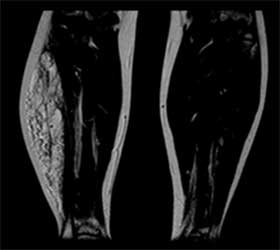

O Eco Doppler (ecografia ou ultrassonografia que analisa os vasos) pode ser usado para estudar lesões superficiais e mostrar as características do fluxo do sangue (veja na imagem superior um eco-doppler de uma anomalia vascular fibro-adiposa na perna).